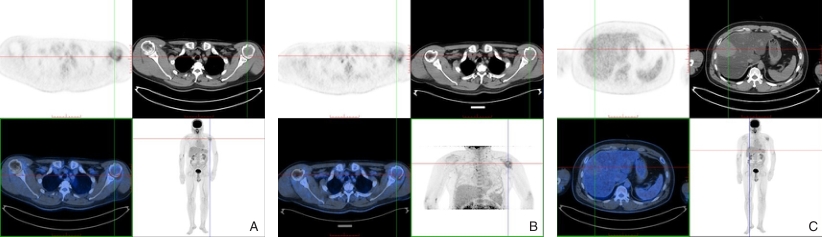

图2 全身PET/CT结果 A:左侧肱骨病灶处显像剂分布浓聚;B:延迟显像增高<25%;C:肝脏内较大稍高密度肿块影,未见显像剂分布异常浓聚Fig.2 Whole-body PET/CT findings A: Increased radiotracer uptake in the lesion of the left humerus; B: Delayed imaging shows an increase in uptake of less than 25%; C: A relatively hyperdense mass is observed in the liver without abnormal radiotracer uptake